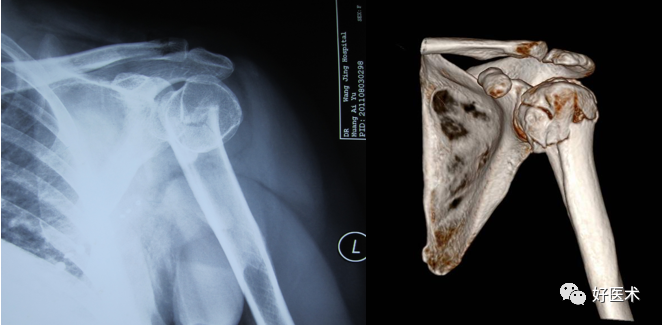

2.AO分型

AO分型

临床表现及诊断

诊断依靠症状及放射检查

(2)常见骨折类型

-

结节撕脱骨折

肱骨外科颈或解剖颈骨折

移位骨折

骨折-脱位